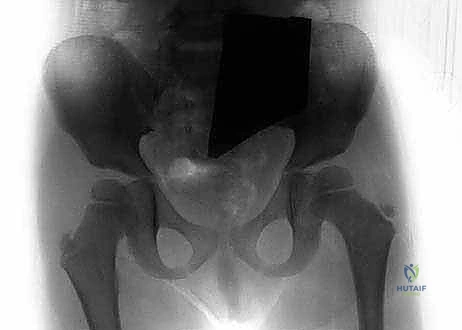

* إصلاح الفخذ الأفحج (Coxa Vara Correction): يقوم الدكتور هطيف بقطع عظمي دقيق في أعلى الفخذ لتعديل الزاوية بين العنق والجسم، وتثبيتها بشرائح ومسامير خاصة بالأطفال. هذا يعيد الشد الطبيعي للعضلات المبعدة ويقضي على العرج.

معرض الصور السريرية لمراحل التثبيت والتطويل:

إحدى الحالات كانت لطفل يبلغ من العمر 4 سنوات، وُلد بفارق طول يتجاوز 7 سم مع عدم استقرار في مفصل الورك (Coxa Vara). بعد تقييم دقيق، أجرى الدكتور هطيف جراحة لإصلاح زاوية الفخذ وتثبيت الحوض. وبعد عام، خضع الطفل لعملية تطويل باستخدام جهاز إليزاروف. بفضل التزام الأهل بخطة العلاج الطبيعي والمتابعة الدورية في صنعاء، تمكن الطفل من المشي على قدمين متساويتين، وتخلص من العرج تماماً، وهو الآن يمارس رياضة كرة القدم مع أقرانه.

معرض إضافي لصور الأشعة والمتابعة الدقيقة للحالات: